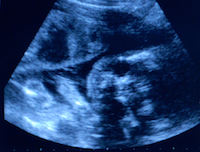

Gynäkologischer Ultraschall

Der moderne Ultraschall ist in der Gynäkologie für eine qualitativ hochwertige Diagnostik unverzichtbar.

In der Frauenheilkunde nutzen wir den Ultraschall zur Untersuchung der Brust und der weiblichen inneren Genitalorgane. Wir führen auch die gynäkologische Doppleruntersuchung in unserer Praxis durch.

Vaginaler Ultraschall

Die Tastuntersuchung des Unterleibs bietet nur einen groben Anhalt für Veränderungen. Insbesondere Geschwülste der Eierstöcke lassen sich nicht immer sicher erkennen. Veränderungen innerhalb der Gebärmutter wie Auffälligkeiten der Gebärmutterschleimhaut (Polypen) und des Gebärmutterkörpers (Myome) lassen sich durch die Tastuntersuchung gar nicht erfassen. Deshalb führen wir eine Ultraschalluntersuchung mit einer speziellen Scheidensonde durch, die eine deutlich höhere Sicherheit bietet. Findet sich tatsächlich eine Auffälligkeit am Eierstock oder an der Gebärmutter, beurteilen wir, ob eine Operation notwendig wird oder aber eine Kontrolluntersuchung ausreichend ist.